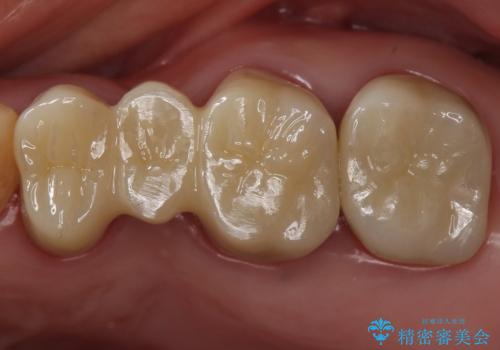

- 左上4567 フルジルコニアクラウン、フルジルコニアブリッジ 77000円×4本 費用は治療当時の料金となります

今回は目立つ虫歯がなかったため、形を整えて白い被せものを装着しました。

他の銀歯も白くしていきたいとのことで、現在前向きに検討されています。